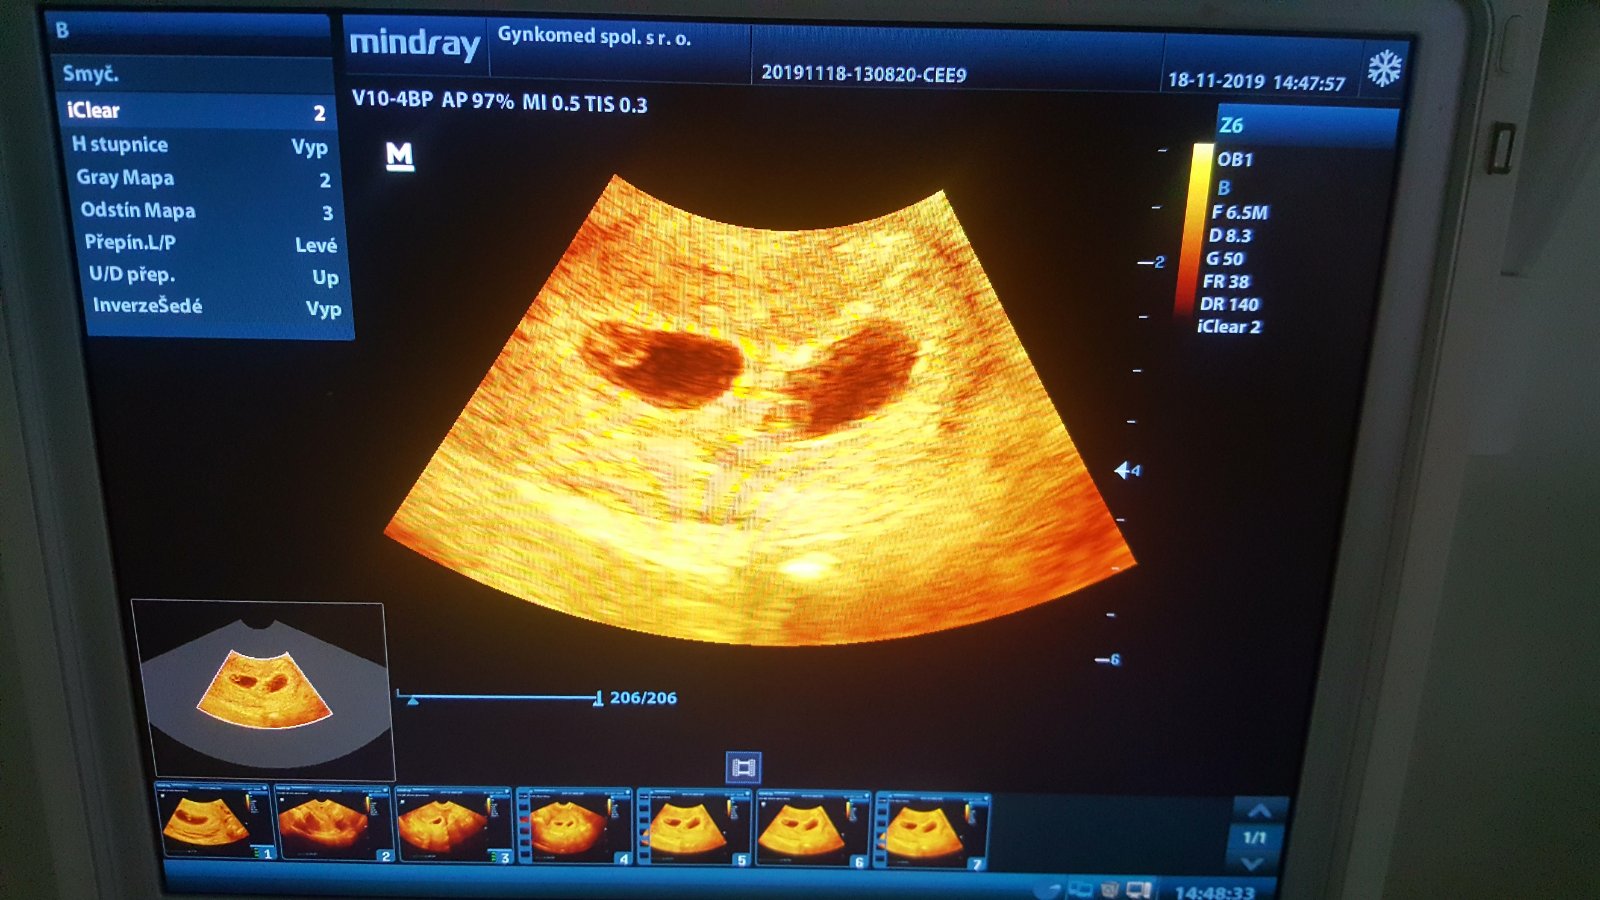

@katkaba1 bozinku ja keď toto vidím až mi srdiečko 🧡 podskočí je to nádhera a ja by som to hneď prijala♥️♥️gratulujem